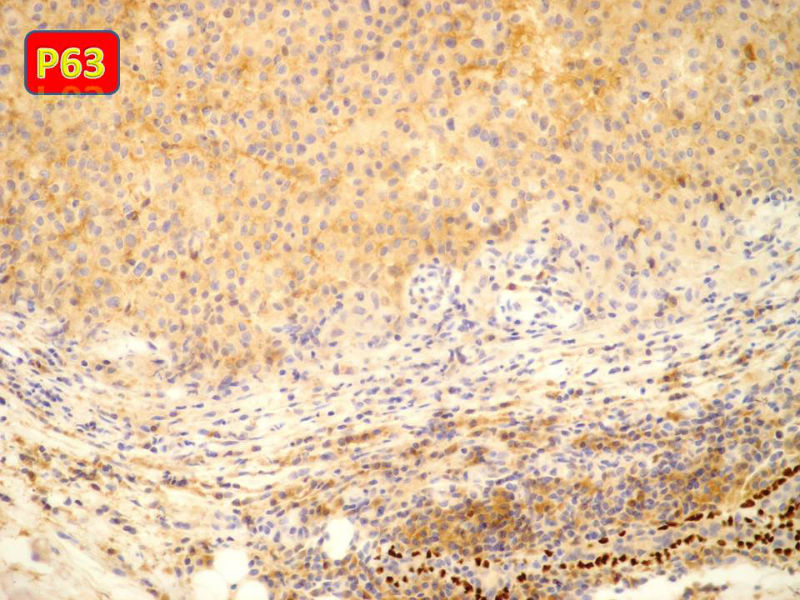

免疫组化